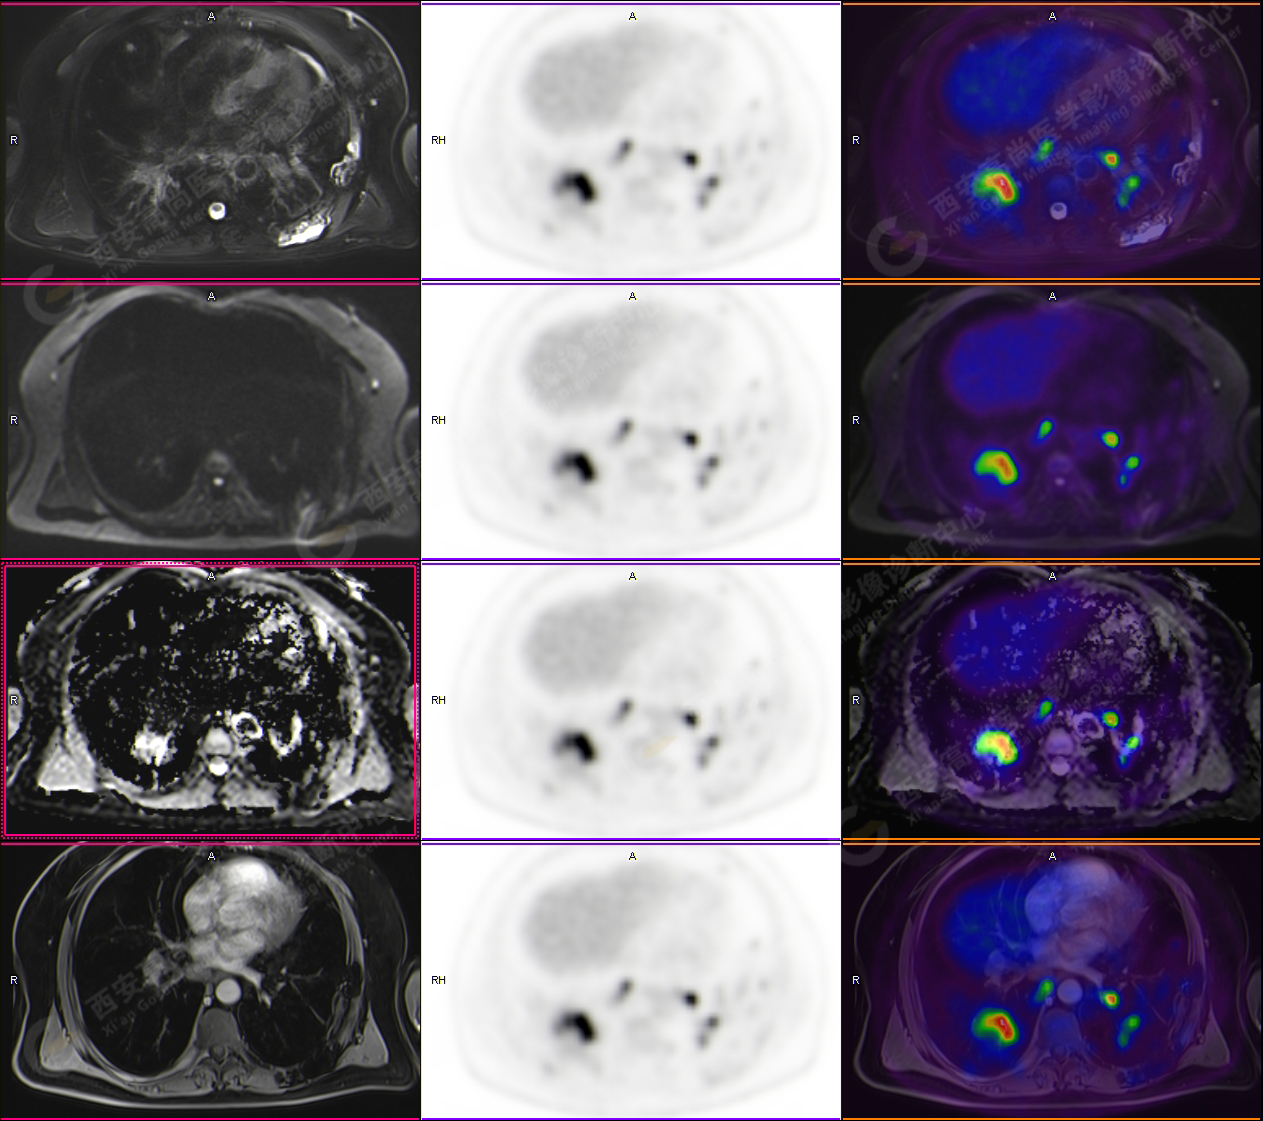

PET-MR圖像